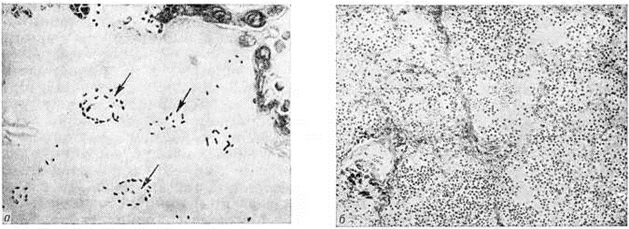

Для Пневмония при острых вирусных респираторных инфекциях (гриппе, парагриппе, респираторно-синцитиальной и аденовирусной) наиболее характерно поражение эпителия слизистой оболочки дыхательных путей и альвеолоцитов. В результате внутриклеточного размножения вирусов происходит повреждение этих клеток с развитием дистрофических и некротических изменений. При благоприятном течении заболевания через несколько дней в них возникают реактивные изменения в виде уплотнения цитоплазмы вокруг участка повреждения — фуксинофильные включения) (рисунок 3, б). Наряду с этим наблюдаются умеренно выраженные воспалительные изменения слизистой оболочки дыхательных путей с преобладанием нарушений кровообращения в виде полнокровия сосудов, выпотевания серозной жидкости в просвет альвеол и небольших кровоизлияний. Отмечаются также небольшие скопления нейтрофильных лейкоцитов и альвеолярных макрофагов. В результате нарушения образования сурфактанта (смотри полный свод знаний) возникают небольшие ателектазы (смотри полный свод знаний), большей частью неполные,— дистелектазы (рисунок 3, в), что особенно выражено у детей раннего возраста, а также компенсаторное очаговое расширение альвеол в других участках лёгких. Макроскопические изменения при этом незначительны и заключаются в основном в катаральном воспалении дыхательных путей и образовании в лёгких небольших участков уплотнения темно-красного или синюшного цвета. Наиболее характерной чертой вирусной Пневмония является гигантоклеточное превращение поражённых эпителиоцитов.

При гриппе поражённые клетки несколько увеличиваются в объёме, в случае же отторжения превращаются в крупные одноядерные клетки, значительно превышающие по размерам обычные альвеолярные макрофаги (рисунок 3, г). Для парагриппа типичны подушкообразные разрастания, сосочковидные выросты слизистой оболочки. При респираторно-синцитиальной инфекции они ещё более выражены. При аденовирусной Пневмония происходит образование крупных одноядерных клеток (гигантоклеточный метаморфоз альвеолоцитов), а также выраженное накопление экссудата (рисунок 3, д). При выздоровлении происходит регенерация эпителия дыхательных путей. Вначале выявляются недифференцированные уплощённые эпителиальные клетки, располагающиеся обычно в несколько рядов (рисунок 3, е), которые в дальнейшем дифференцируются .

Изменения, сходные с морфологический изменениями при вирусной Пневмония, наблюдаются при микоплазменной Пневмония — респираторном микоплазмозе (смотри полный свод знаний Микоплазменные инфекции). Для неё также типично внутриклеточное размножение возбудителя (рисунок 4), хотя возможно и внеклеточное. Поражения носят характер десквамативной Пневмония при весьма умеренных макроскопических изменениях (цветной рисунок 3—5; 6—10).